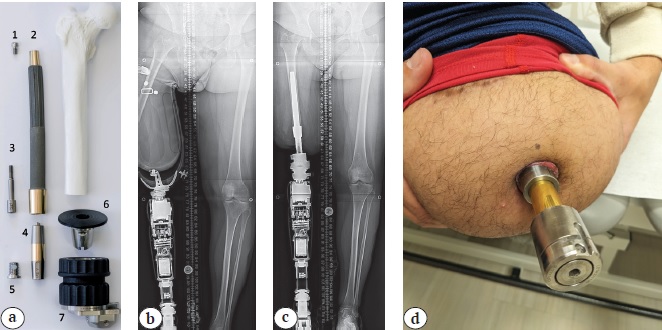

An additional concern is whether there is a minimum bone length to achieve stable osseointegration. There is no apparent consensus on what defines a short limb, but standard press-fit implants are 14 cm long. There are two strategies reported by two different groups. One strategy as reported by J.S. Hoellwarth et al. [56] is to lengthen a bone prior to osseointegration. In that study, 10 patients were lengthened by an average of 52 mm, requiring about a year from starting lengthening to the TOFA surgery. All patients achieved independent ambulation without any apparent compromise to implant stability, but the multiple surgeries and protracted period tempered patient satisfaction. An alternate option, also reported by J.S. Hoellwarth et al. [56], is simply directly performed TOFA for residual bones as short as 5-6 cm (Figure 3). They reported no association between residual bone length and post-TOFA reoperation rates, including such issues as aseptic loosening, periprosthetic fractures, or infections. A true minimum bone length remains uncertain, and greater experience will likely eventually help elucidate possible factors contributing to a potential limit.

Figure 3. Short residual bone for osseointegration:

a — X-ray in the anterior-posterior view of the right femur identifying almost no bone beyond the lesser trochanter. She was a functional hip disarticulation patient due to the inability to wear a socket;

b — this patient had partial hardware removal with simultaneous osseointegration, achieved excellent fixation and now ambulates without an assistive device; c — X-ray in the anterior-posterior view of the left tibia for a patient with minimal bone distal to the tibial tubercle. His residual limb was too short to use tibia-level prosthesis and he was considering transfemoral amputation prior to consultation for osseointegration;

d — the patient also achieved ambulation without an assistive device with a press-fit osseointegration implant